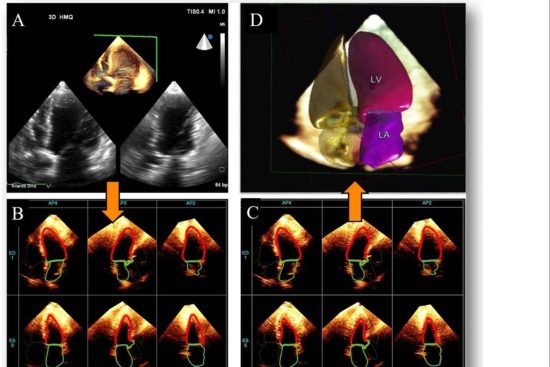

La línea de ecógrafos de SCPmedical se caracteriza por su portabilidad, conectividad y facilidad de manejo. Los modelos inalámbricos permiten trabajar en movimiento, sin cables, optimizando el espacio y mejorando la higiene en entornos sensibles. A su vez, los dispositivos portátiles ofrecen la posibilidad de realizar exámenes de imagen directamente junto al paciente, tanto en hospitales como en consultas externas, residencias o unidades móviles.